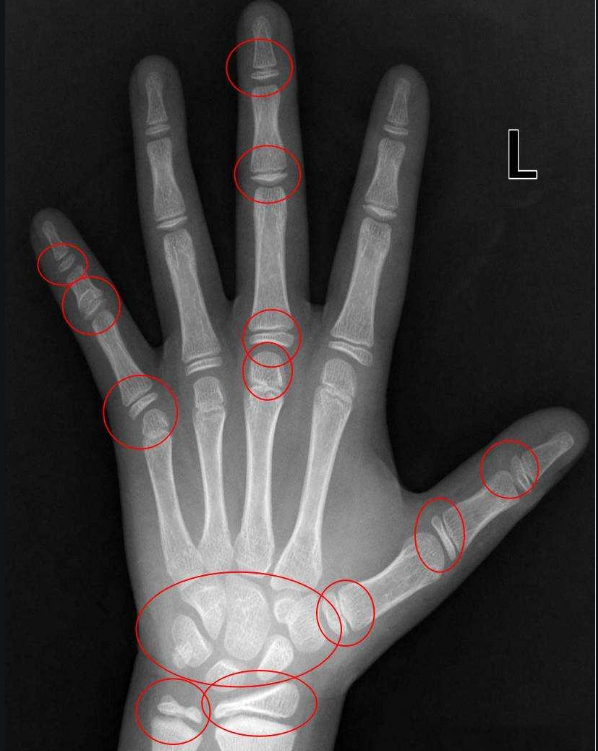

骨龄检测方法

通过拍摄左手(非惯用手)手腕部X光片,观察掌指骨、腕骨、尺桡骨骨化中心的发育情况,从而评估孩子的生长发育状况。